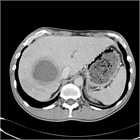

1. 肝膿瘍は、大きく細菌性とアメーバ性の2種類に分けられる。